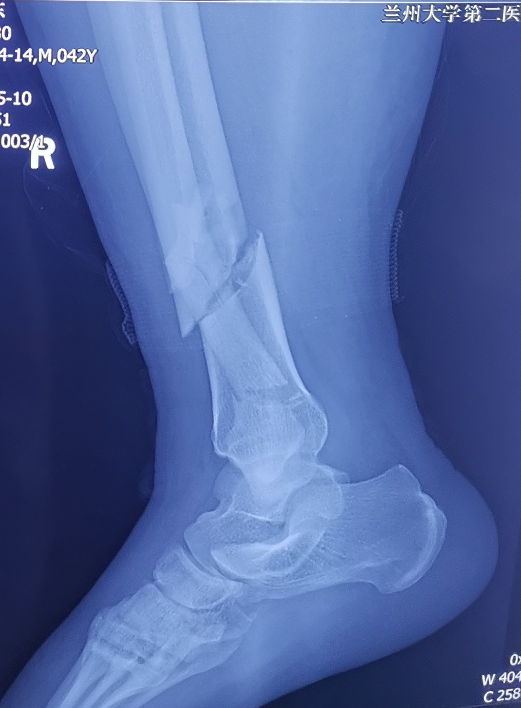

患者,男,42岁,因异物砸伤致右下肢疼痛、肿胀,活动障碍7小时入院。入院后诊断为右胫腓骨远端骨折、右足楔骨骨折、右跖骨骨折、右骰骨骨折。入院时右侧小腿远端前内侧明显肿胀,局部可见大量张力性水泡。骨科四病区医护人员立即开展病情讨论,并制定详细周密的手术计划,同时在患者及其家属知情同意后,实施胫骨远端骨折逆行胫骨髓内钉内固定术。

小腿远端腓骨骨折治疗多采用切开复位钢板内固定,胫骨骨折可选用MIPPO技术钢板固定、胫骨顺行髓内钉及胫骨逆行髓内钉技术,其中MIPPO技术因患者软组织条件差术前消肿时间过长,顺行髓内钉因骨折线位置较低髓内钉远端把持力不足,同时会一定程度影响膝关节活动。而胫骨逆行髓内钉技术作为国内逐渐发展起来的新技术,在处理胫骨远端骨折时具有软组织损伤小、复位及固定简易等优势,十分适合本症状患者。